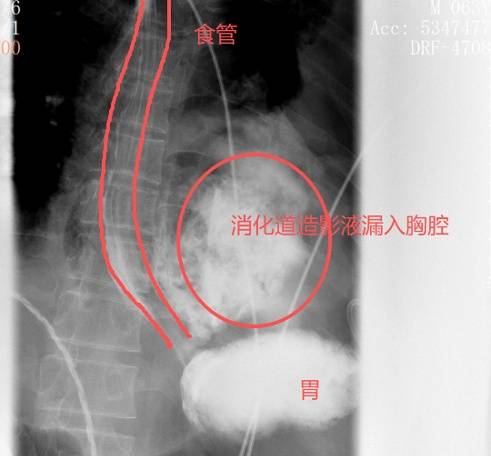

很快,口服钡餐的结果印证了他的判断:钡剂从(cong)食道(dao)下段的裂口处大量漏出,直接进入了左(zuo)边胸腔(qiang)。

图源:腾讯医典

红圈区域(yu)是食物残渣、消化液破(po)入食管(guan)